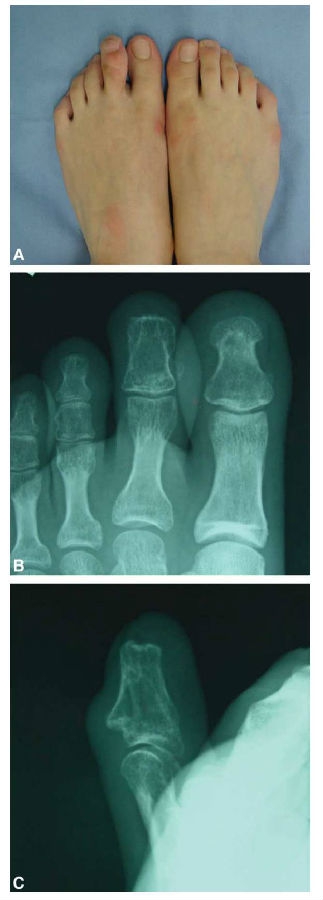

尽管我们推荐截除末节趾骨使巨趾长度和周围保持一致,但是患者希望能保留趾甲。所以我们根据以前移植趾甲修复手指设计了趾甲皮瓣来保留巨趾的趾甲。术前设计皮肤的切口确认趾甲的长度和大小和对侧相等,在全麻和止血带下,趾甲瓣被窃取下来,血管蒂为第二趾的指固有动脉,部分末节趾骨保留在趾甲下面约2毫米,其余的末节趾骨部分从关节处分离解脱。骨头通过钢丝捆扎固定,术后5周去除。术后6个月,患者站立时间产后会有轻微的疼痛和肿胀。在术后12个月后,这些症状改善,患趾大小和对侧接近,骨愈合良好。对手术效果非常满意。